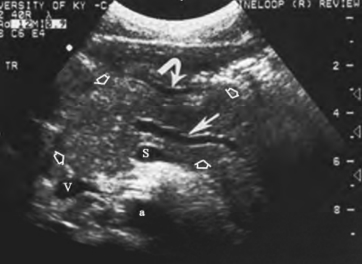

(1)胰腺肿大:胰腺多呈弥漫性肿大(图26-6),亦可某一局部肿大较明显,故切面形态发生明显改变,严重者胰头可几乎呈圆球形。

图26-6 急性胰腺炎声像图

胰腺横切面显示胰腺肿大,回声明显减低